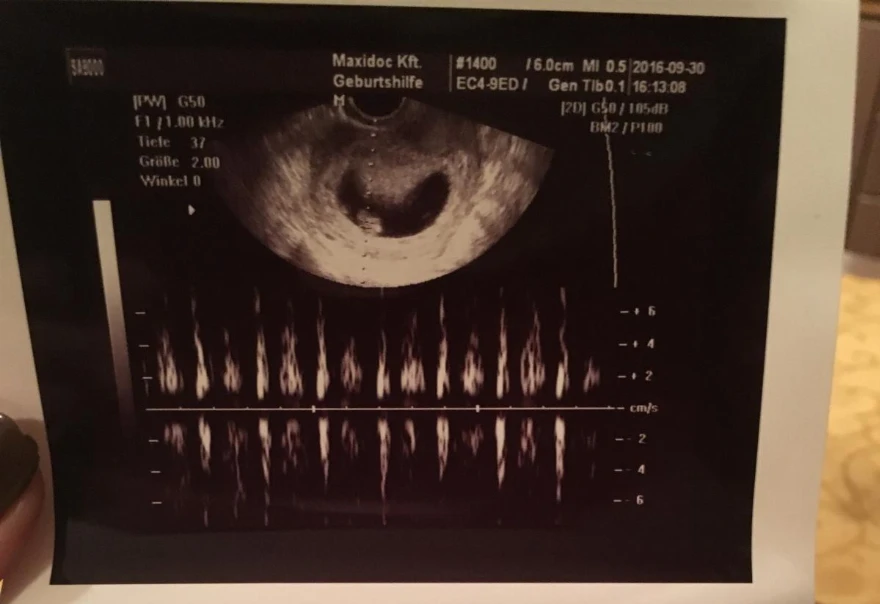

Ekkor varázslatos érzés fogott el, ahogy egy nagy monitoron láttam, amint egy kis krumpli látható a hasamban, akinek dobog a szíve. Rápillantottam a férjemre, és csak arra tudtam gondolni, hogy ez a kis krumplibaba a legcsodálatosabb dolog, ami velünk eddig történt. Láttam a ragyogó arcán, hogy ő is elégedett és boldog.